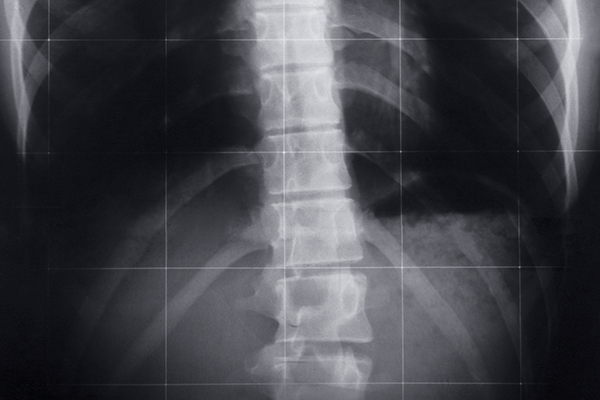

STEP 01. 위치확인

영상 장비로 원하는 척추부위를 정확히 확인합니다.